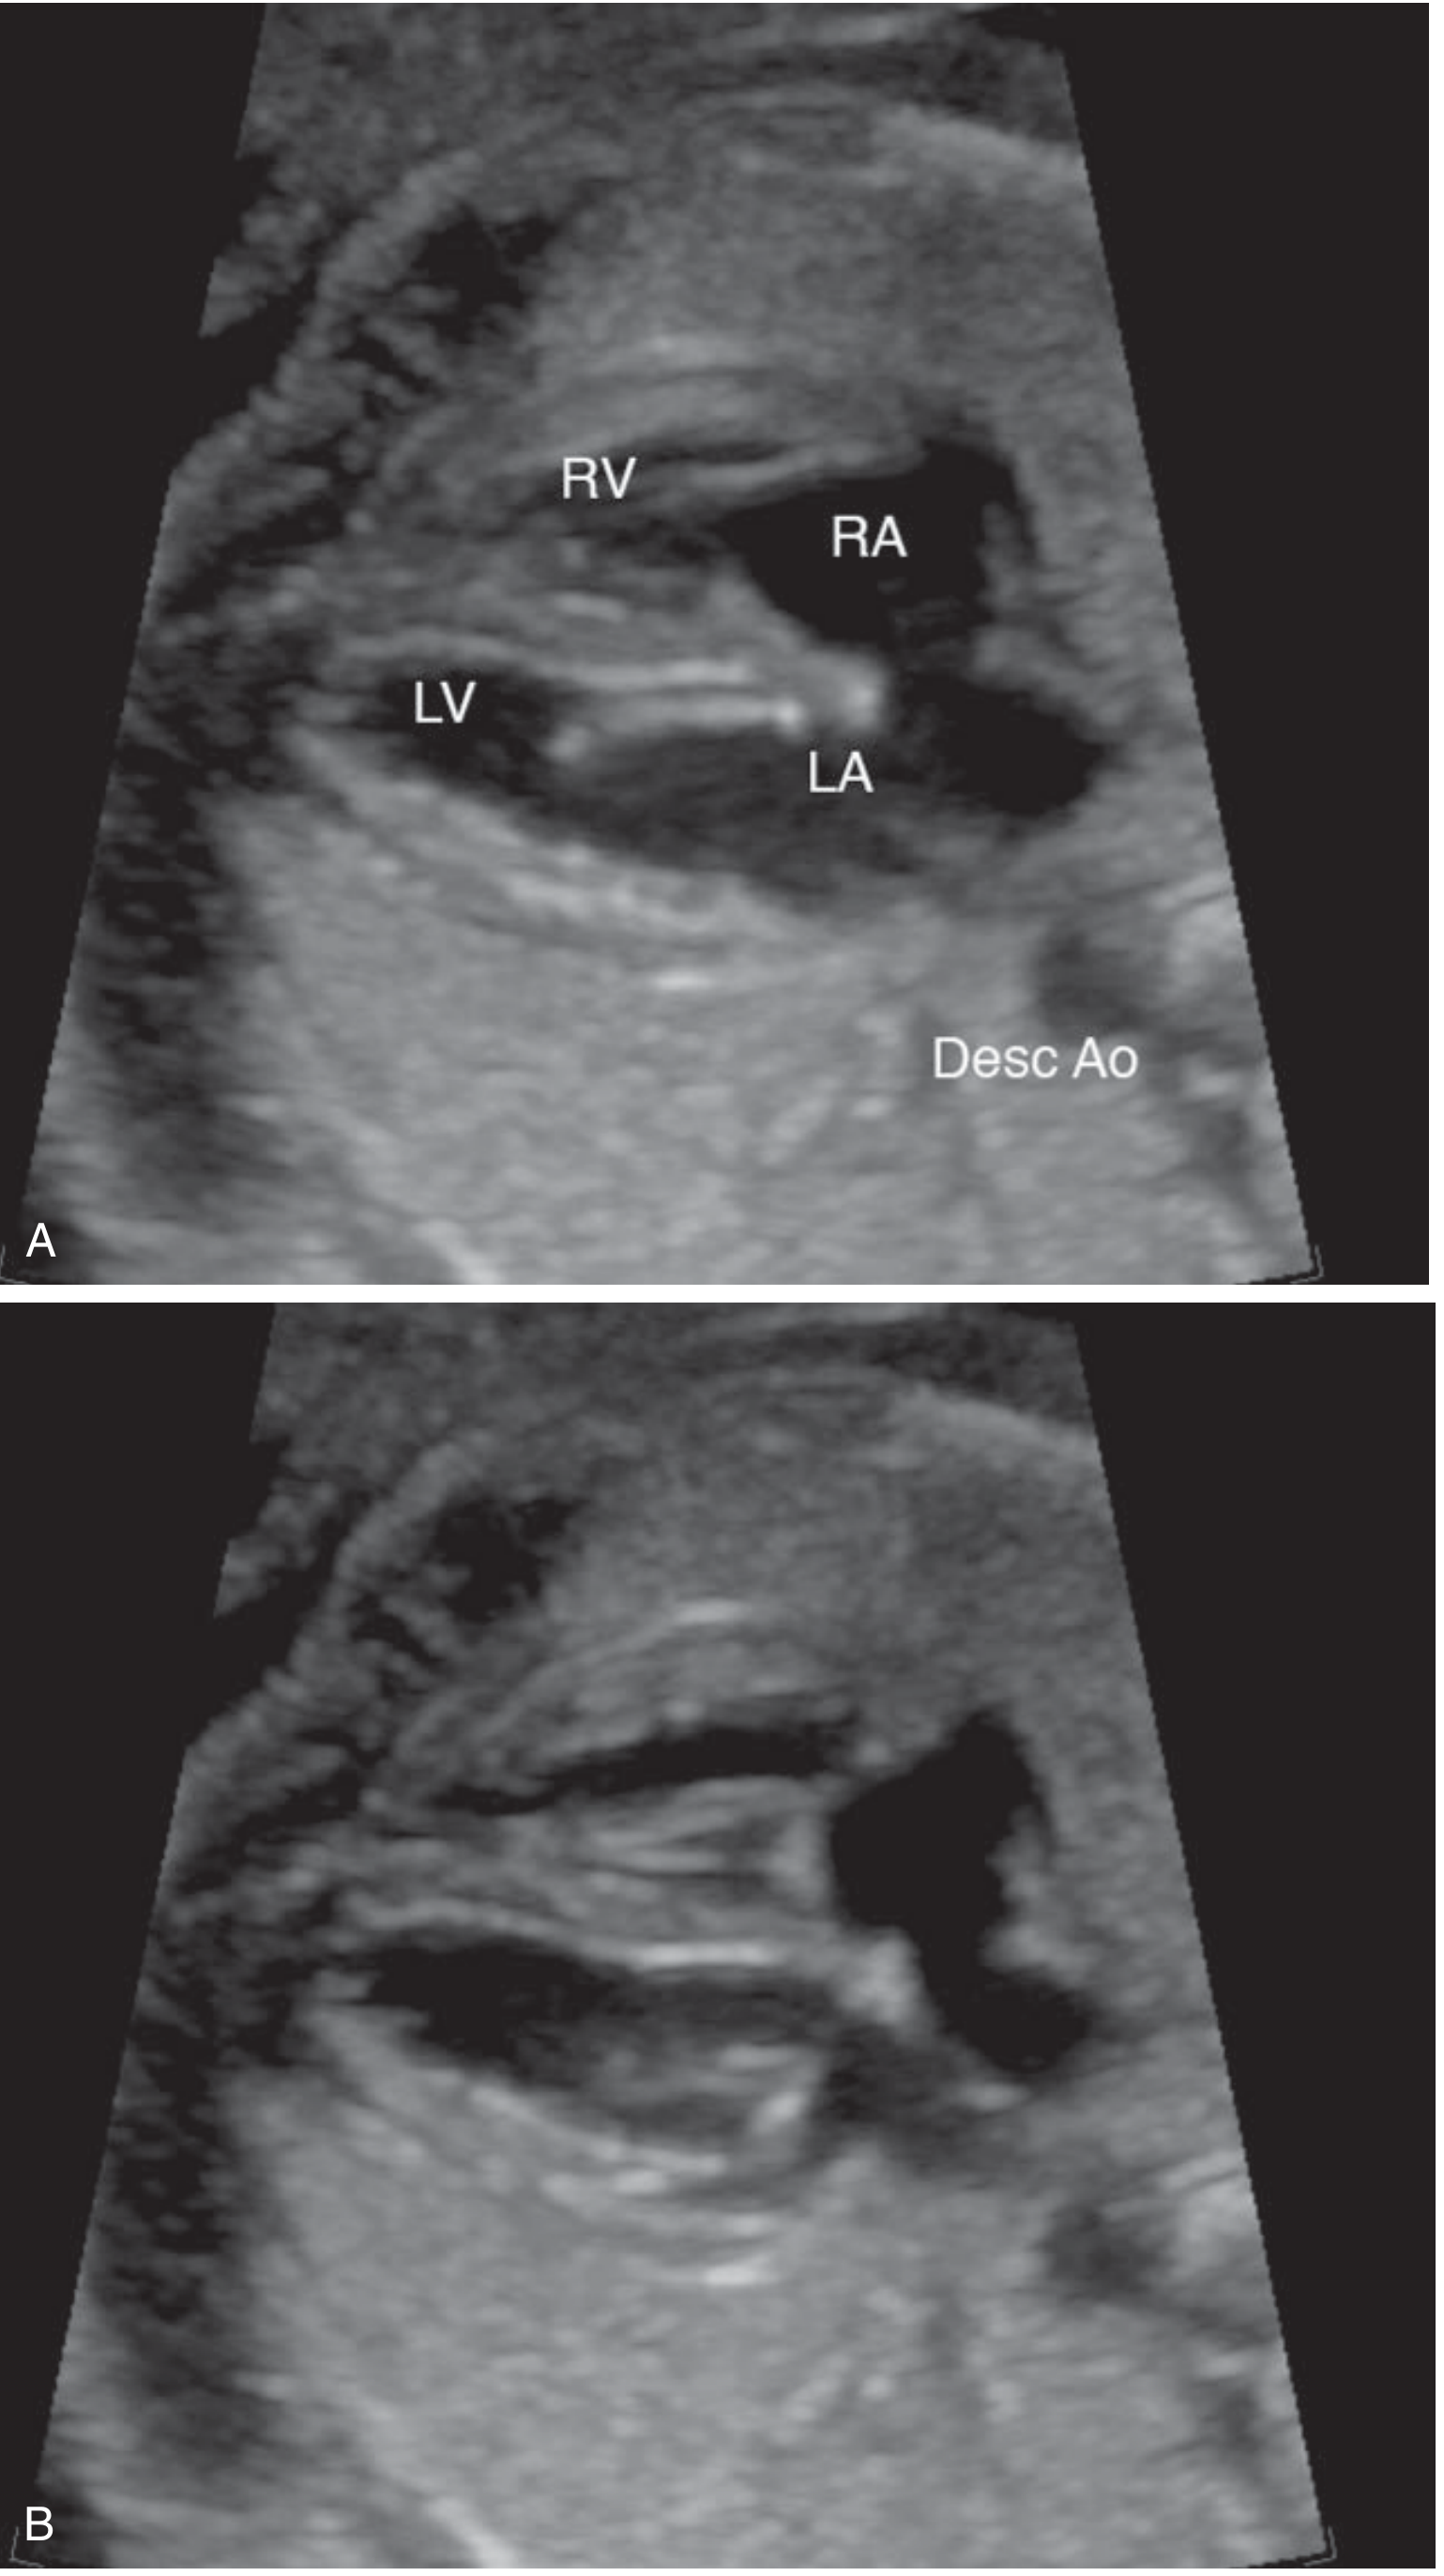

Four-chamber heart view

Figure: Four-chamber heart view in diastole and systole (RV, LV, RA, LA)